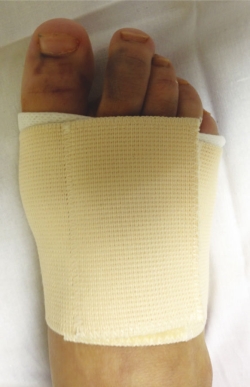

A los 10 días, se retira el vendaje posquirúrgico y se coloca una banda metatarsal que tiene un velcro que permite apretar o aflojar según el edema del pie (Figura 6). Esta faja metatarsal proporciona estabilidad a la artrodesis y el paciente es autorizado a realizar carga completa con el zapato ortopédico y la faja hasta las 5 semanas.

Figura 6. Faja estabilizadora para antepié utilizada en el postoperatorio de la intervención de artrodesis. También es utilizada en postoperatorio de cirugía del hallux valgus.